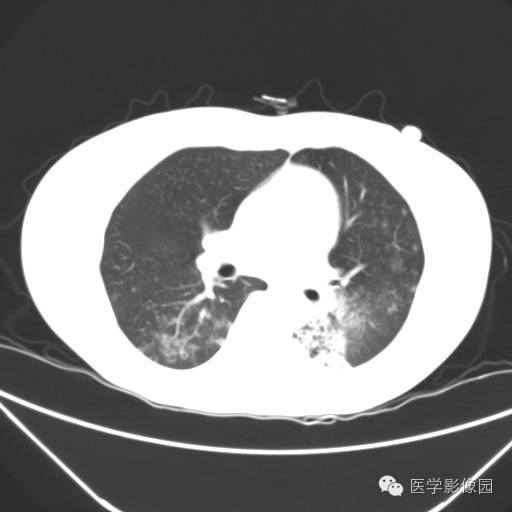

肺叶实变性支气管肺泡癌1例CT影像表现